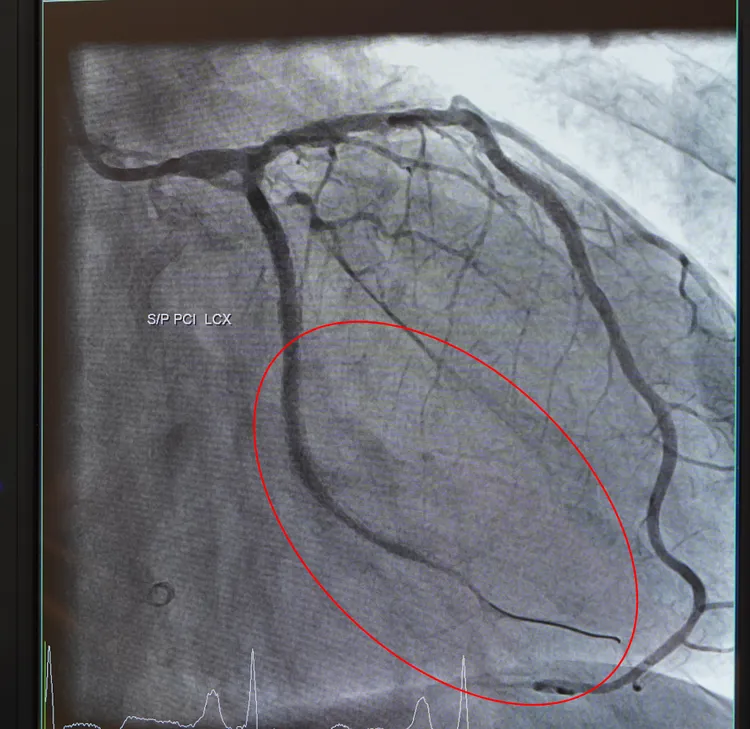

王先生通過健檢,發現心血管阻塞處。院方提供